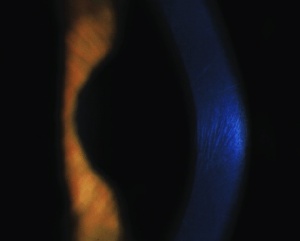

Striae in the normal cornea have been described as few, short, and oblique; striae in the keratoconus cornea are numerous and vertical. Striae in the edematous cornea (Fuch’s dystrophy and bullous keratopathy) are few and oblique (Fig. 1, 2).[3]

It had been previously postulated that striae were due to ruptures in collagen lamellae, but it has been demonstrated by second harmonic generation microscopy (SHG), polarization-resolved SHG (P-SHG), and scanning electron microscopy (SEM) that striae are due to folds in collagen lamellae (Fig. 3).[3]

Striae can be diagnosed with slit-lamp, optical coherence tomography (OCT), full-field optical coherence microscopy (FFOCM), and confocal microscopy (CM). OCT has the least sensitivity in detecting striae as the width of the striae is at the lateral resolution limit for OCT. Striae appear as dark bands on CM, FFOCM, and OCT because the undulated lamellae reflect light away.[3]